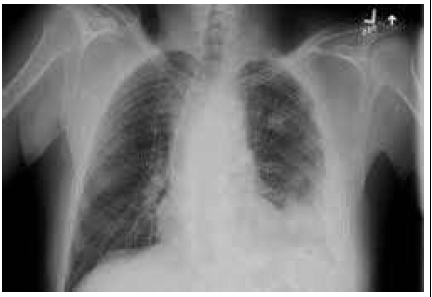

Uma paciente CLA, feminina, de 67 anos de idade, apresenta quadro de pneumonia bacteriana adquirida na comunidade. Durante internação para tratamento com antibioticoterapia endovenosa, evoluiu com manutenção de quadro inicial de dor pleurítica e com febre no 3.º dia de internação; seus exames laboratoriais estão sem alterações. Foram feitos exames complementares, conforme se vê na imagem a seguir. Foi realizada toracocentese, a qual evidenciou líquido purulento, pH < 7,20; DHL > 1.000 UI/L; e glicose < 40 mg/dL com bactérias presentes e cultura positiva.

Com base nesse caso hipotético, assinale a alternativa correta.